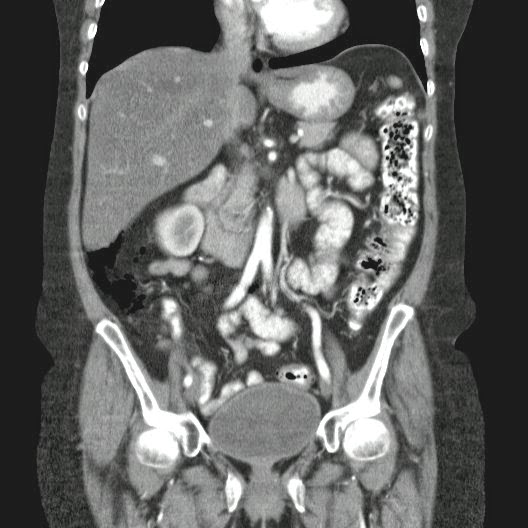

Paciente con antecedente de ALIF (Fusión lumbar intersomática anterior) 360 grados L5-S1 hace siete meses, quién presenta herida de abordaje anterior con dehiscencia de sutura, con cierre por segunda intención, quien consulta por cuadro clínico de dos días de secreción purulenta en herida quirúrgica, niega fiebre, niega otras sintomatología, refiere episodios previos similares.

Paciente en POP de ALIF L5-S1 quien presento dehiscencia de la herida abdominal con ISO superficial ya tratada, sin embargo persiste con dehiscencia y desde ayer con supuración asociado a fiebre subjetiva. Se realiza eco abdominal con colección en pared sugestiva de absceso, elevación de RFA por lo cual se considera se debe hospitalizar para manejo antibiótico, drenaje de la colección, manejo médico y vigilancia neurológica.

- ¿Hallazgos Escanografia?

2. Hay una colección de la pared abdominal en el flanco derecho, que realza en la periferia con el contraste, e intraabdominal tiene aire pero no me parece colección intraabdominal porque la grasa no está alterada.

3. Recomendado: Drs. JOSÉ M. ZUÑIGA A.1, FRANCO ORELLANA G.1, MARCELO CASTRO S.3, ROLANDO SEPÚLVEDA D.4, HORACIO RÍOS R.4, Int. VELIA SALDÍAS H.2. Neumatosis Intestinal: Caso Clínico-Radiológico. Pneumatosis intestinalis. A case report. Rev Chil Cir v.61 n.1 Santiago feb. 2009